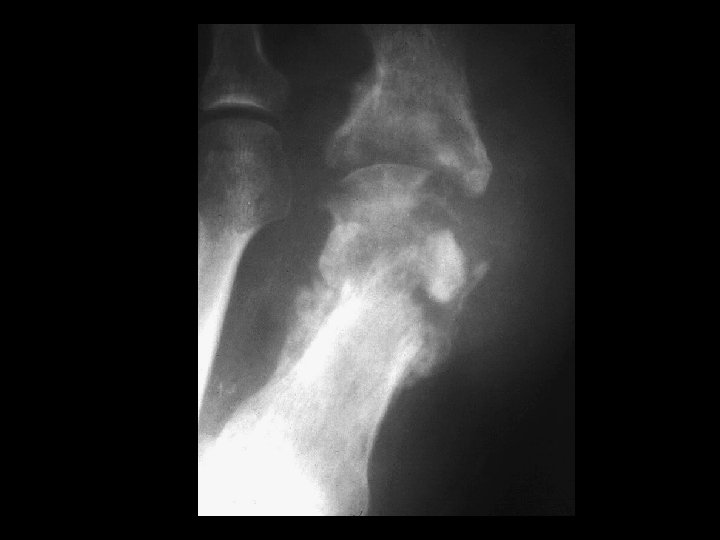

Septic Arthritis • Findings: – Lytic and sclerotic destruction of the great toe MTP joint – Joint space narrowing – Periosteal reaction – Soft tissue swelling • ddx: – Charcot joint